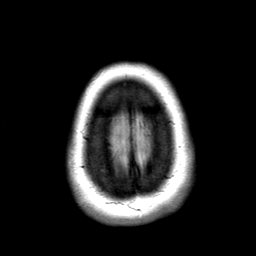

Cerebral hemorrhage, MR Study mr-pd -- Slice #22

[Home][Help][Clinical] Slice 22